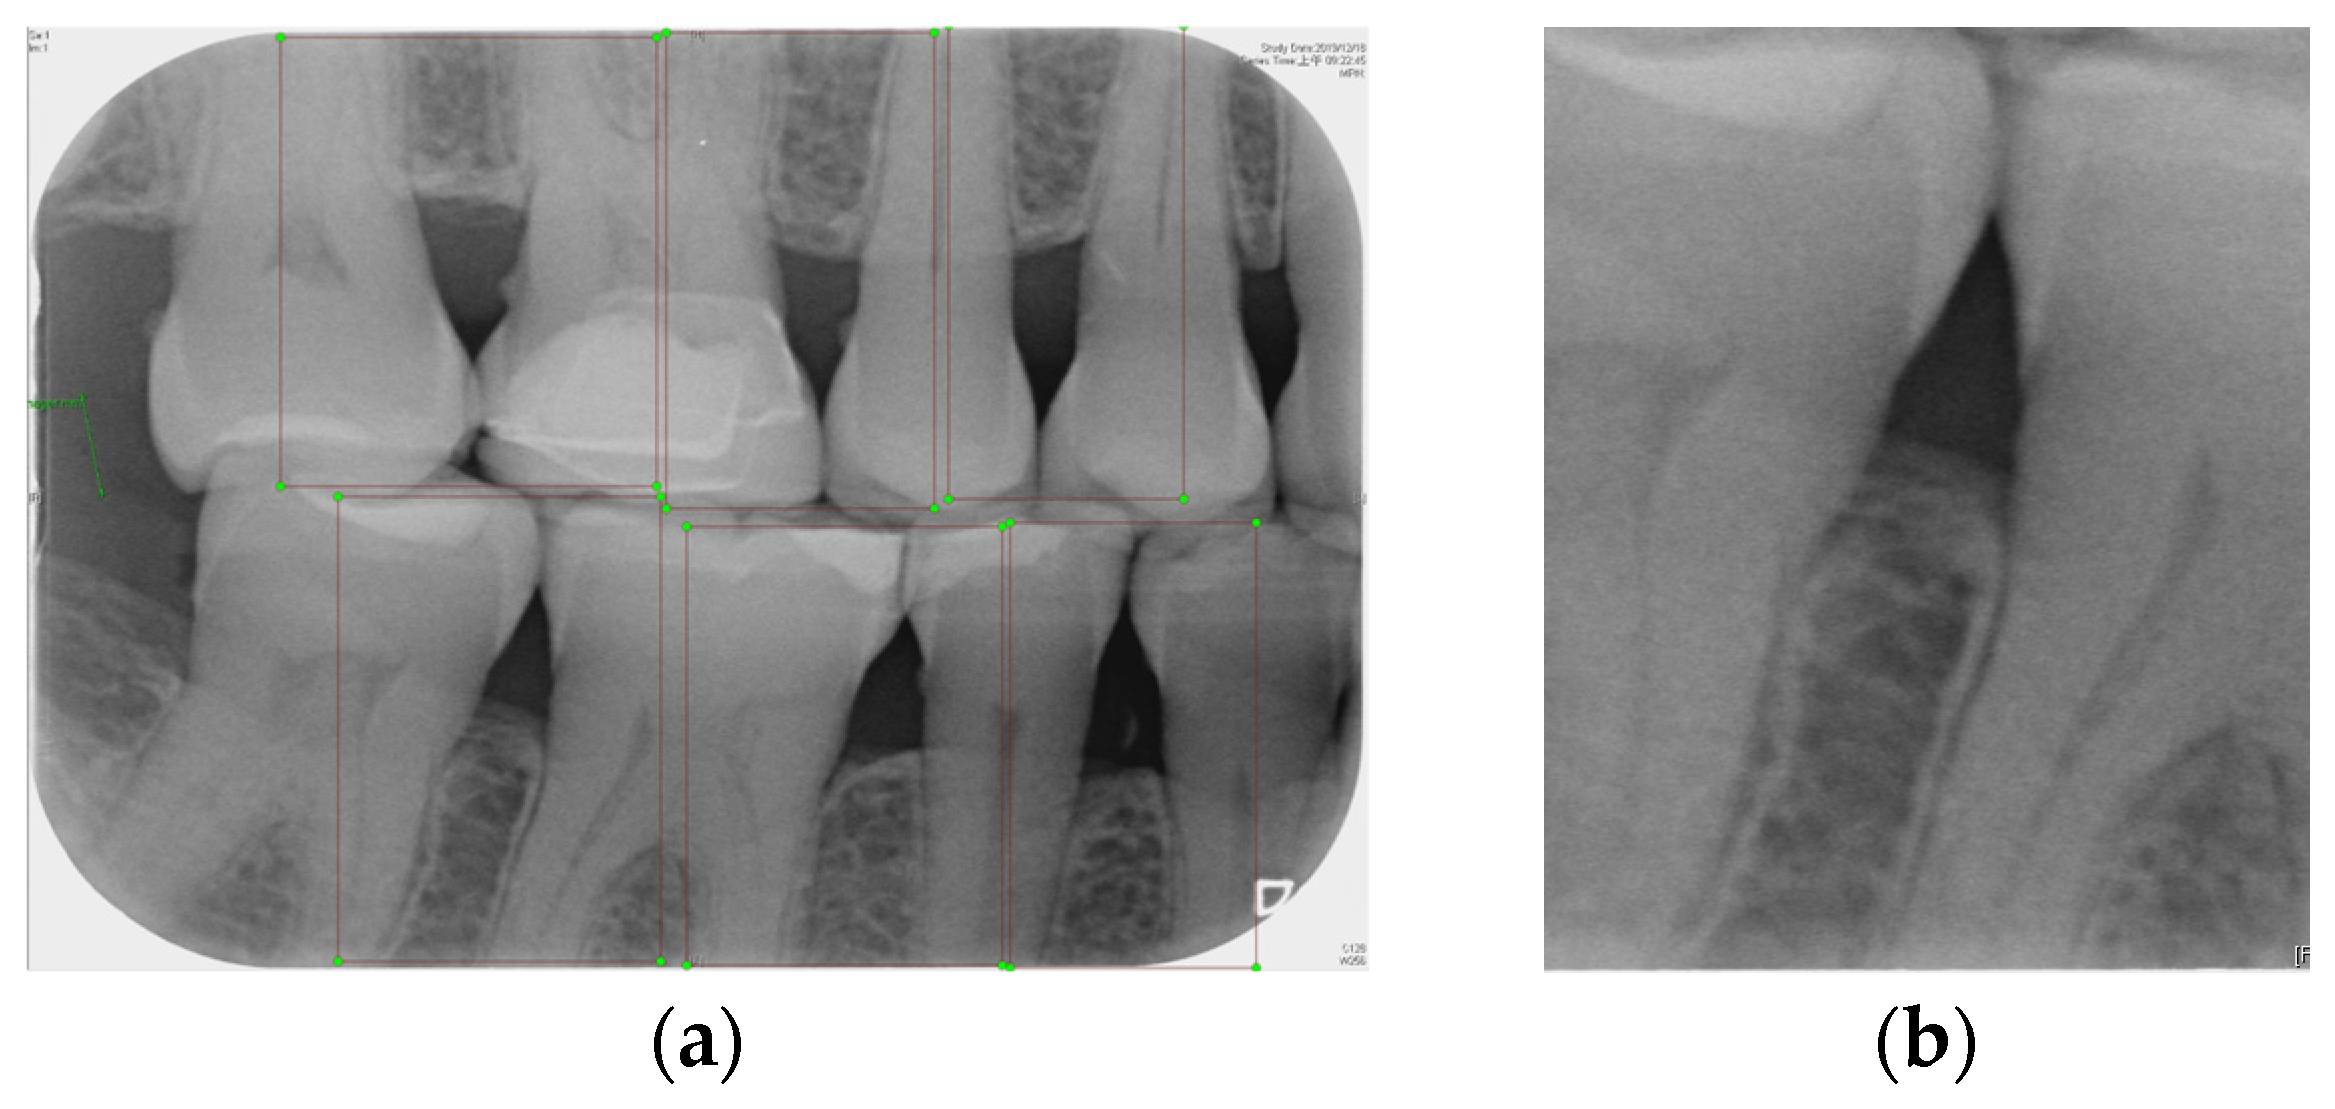

2.2.1. Annotation of Tooth

Labeling was used as a tool, and by utilizing the rectangular tool, the marking range was from a single tooth section to another tooth section, which helps to accurately mark the actual condition of the gingiva around the middle of the tooth. Finally, the image was saved as a YOLO file and labeled as shown in Figure 2a. This process highlights the target area in the image and provides clearer information for CNN training.

2.2.2. YOLOv8 Model Training

Numerous object detection models have been developed, such as the R-CNN series, Single Shot MultiBox (SSD), RetinaNet, and YOLO. Due to the complexity and variability in tooth alignment in each patient, the gums need to be separated at the BW film; YOLOv8 is the best model utilized in BW image segmentation for Angular Erosion. The YOLO model has an advantage in detecting the foreground and is highly efficient in considering the global information of the image and making judgments, and it also utilizes an anchor-free design. In the past, anchor frame detection was utilized to envelop various objects with predefined anchors. Regression adjustment was carried out through a series of operations, and the most accurate frames were retained using non-maximum suppression. Anchor-free detection predicts the center point of an object directly from the image to learn its location and size. This method helps detect objects with greater accuracy in various complex scenes, such as accurately locating teeth. Target detection of the vertical biting airfoil image is then performed by the trained YOLO model, as shown in Figure 2b.

Figure 2. Image annotation and segmentation. (a) Image Annotation Diagram. (b) The tooth segmentation result.